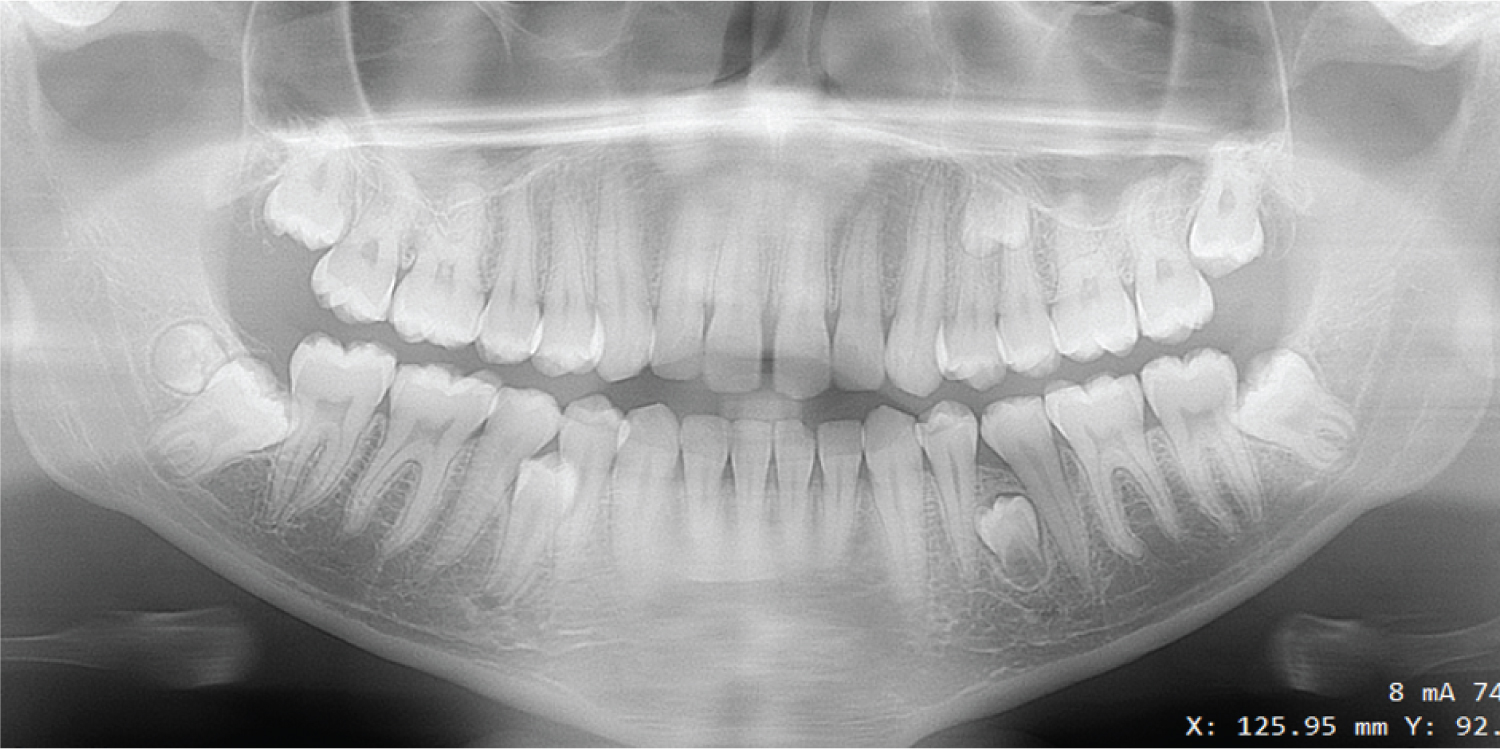

Hyperdontia was observed in 45 (4.8%) patients. Out of them, 36 (60%) patients had one supernumerary tooth, 07 (15.6%) patients had two, 01 (2.2%) had three teeth and another one (2.2%) had more than three (Figure 3). They were observed unilaterally in 37 (82.2%) patients and bilaterally in 08 (17.8%) patients. Moreover, supernumerary teeth were more common among 14-18 years aged subjects (n = 29, 48.3%).

Figure 3: Panoramic radiograph with multiple supernumerary teeth. View Figure 3

In those 45 patients, 60 supernumerary teeth were found. Of those 60 teeth, 38 were found in the upper arch and the rest was in the lower arch. The most common shape was conical (40%), followed by supplementary (33.3%), tuberculate (13.3%), distomolar (10%) and odontomes (3.3%).